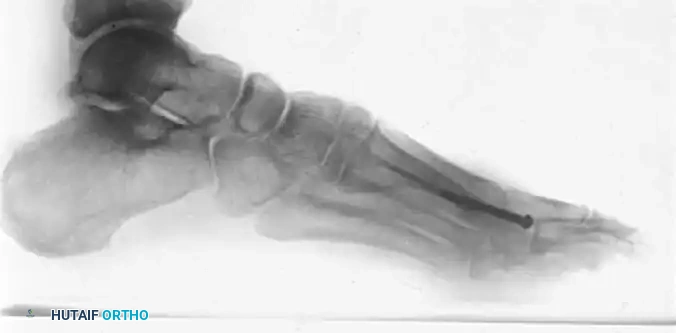

Standard weight-bearing radiographs (anteroposterior, lateral, and oblique views) are essential to evaluate the extent of joint space narrowing, the size of the dorsal exostosis, and the presence of loose bodies.

Image

Anteroposterior and oblique views demonstrating severe hallux rigidus with extensive periarticular osteophyte formation and joint space obliteration.